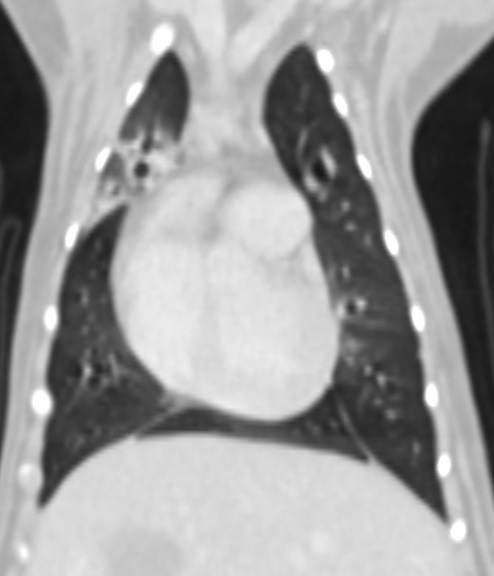

• 慢性咳嗽 支氣管肺炎 綠膿桿菌 電腦斷層掃描

慢性咳嗽 支氣管肺炎 綠膿桿菌 電腦斷層掃描